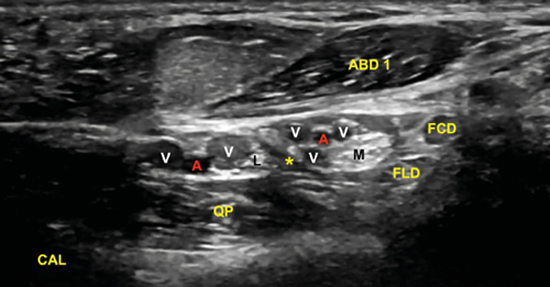

La imagen sonográfica se centrará en el espacio situado bajo la fascia profunda del músculo abductor del primer dedo, por donde discurrirán los haces neurovasculares plantar medial y plantar lateral, diferenciados y separados por el septo de Heimkes o interfascicular3. El nervio plantar medial se muestra con mayor sección que el nervio plantar lateral, y las venas laterales con mayor luz que las mediales (Figura 14).

Figura 14. El septo interfascicular (*) parte desde la fascia profunda del músculo abductor del primer dedo (ABD 1) hacia el tendón flexor largo del primer dedo (FLD) dividiendo la cámara superior de la cámara inferior, donde respectivamente se encuentran el haz neurovascular plantar medial (M: nervio plantar medial; A/V: arteria y venas plantar medial) y el haz neurovascular plantar lateral (L: nervio plantar lateral, A/V: arteria y venas plantar lateral). En profundidad, el músculo cuadrado plantar (QP) y la superficie del calcáneo (CAL).